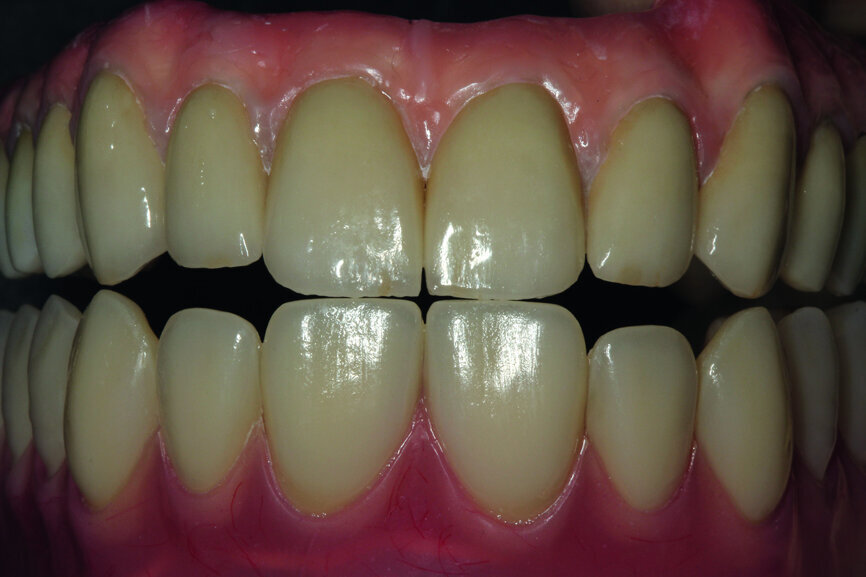

Fig. 24: Final restoration—frontal view.

Fig. 25: Magnification showing precision in the making of the crowns and in veneering by means of pink composite.

After the model was analysed, we proceeded to analyse the fitting and the aesthetics in the mouth of the patient. Carrying out such a test makes a lot of sense, especially in a dynamic way, and by asking the patient to make various facial movements, such as smiles and grimaces, we can assess the properties of the course of the border line of the zenith of the teeth and the transition into a gingival garland. It is of real importance as at this stage that we can plan the process of covering the construction with pink porcelain or composite (Figs. 15–17).

After the test, we sent the construction to a prosthetic laboratory with detailed guidelines for veneering. To achieve the proper location of the pink veneering it was necessary to place the porcelain crowns onto the bar and model the border line for the gingival garland (Figs. 18–20). Due to the fact that the prosthesis constituted the ideal shape of the teeth, it was worth comparing it with the final prosthetic work and assessing the details of the whole work process before the patient sits comfortably in the dental chair (Figs. 21–25).

If the quality of the work satisfies our expectations, we may proceed to the handing-over stage and perform the functional and aesthetic analysis, both intra- and extraorally. A perfect conclusion to the treatment process is the receipt of a complete set of OPG X-rays taken before, during and following treatment (Figs. 29–32).